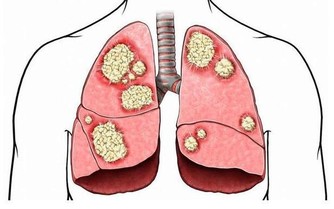

3、維生素A可抗肝癌

研究表明,維生素A能保護肝臟,阻止和抑制肝臟中癌細胞的增生。每天喝一杯牛奶就可以滿足肝臟對維生素A的需求。

動物肝臟、魚肝油及乳製品中也含有大量維生素A;番茄、胡蘿蔔、菠菜等含有維生素A的前體胡蘿蔔素。